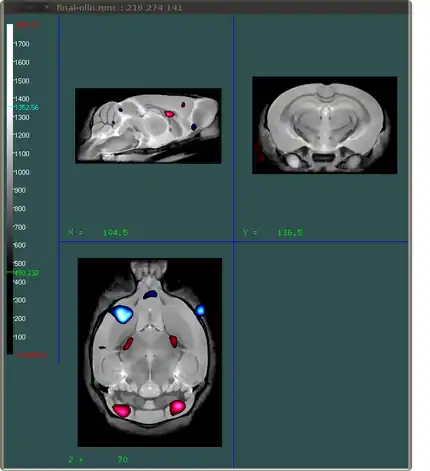

What we want to do is create an image that shows which areas of the brain have a certain t-statistic related to them. Ideally we want to show areas that have negative t-stats and positive t-stats using different colours. The end result should look something like this:

You can load multiple files into Display. In the example above the red shows areas where the t-statistics are at least 4 (and thus positive), and the blue areas indicate areas where the t-statistics are at most -4. All this information comes from one file: the tstats.mnc file. In order to create two different colours using that one file, you will have to load it in twice in Display. That is the first step